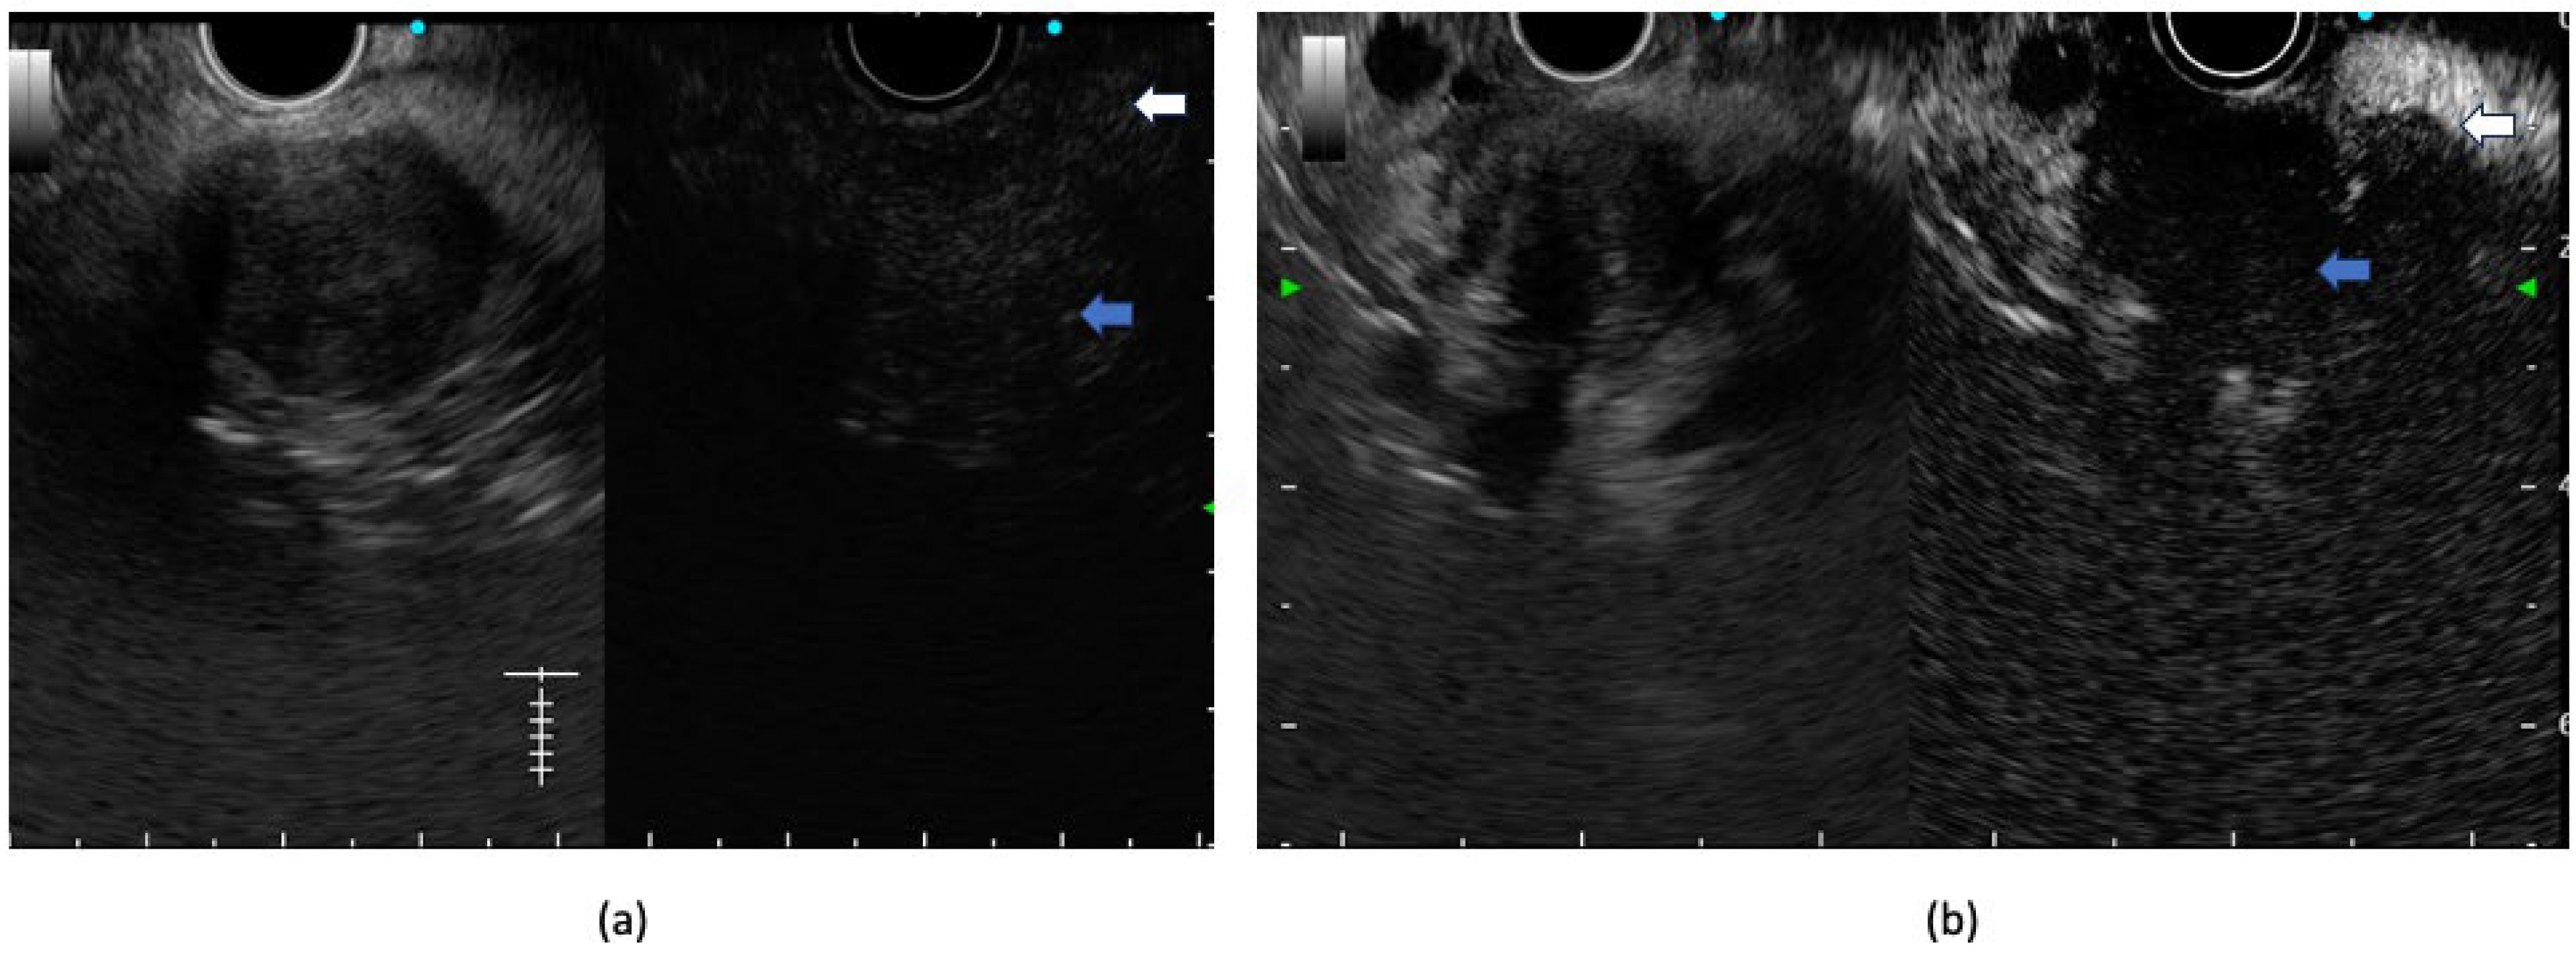

4. Role of Contrast-Enhanced EUS

5. EUS Elastography